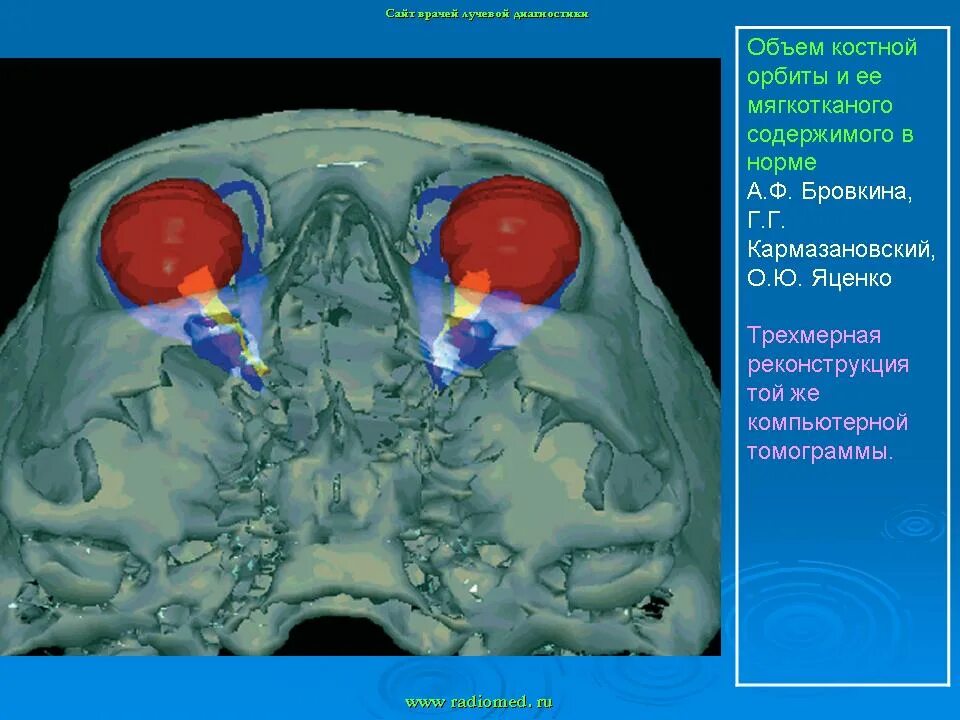

Данные кт